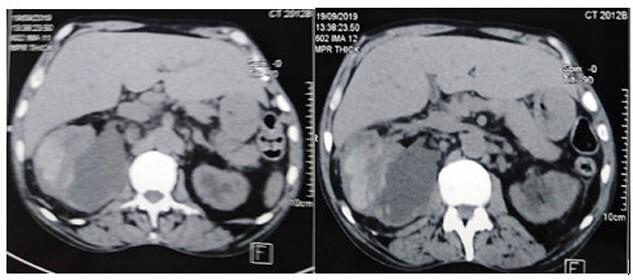

The double-J ureteral stent is a standard procedure in daily urological practice. Although considered as safe, this approach is fraught with several complications. These complications are of limited severity and resolve with symptomatic treatment. In some cases, serious and life-threatening complications, such as infection and subcapsular hematoma, can occur. In the literature, a few cases of subcapsular renal hematoma secondary to ureteral stent insertion have been reported. Herein, we report a case of renal subcapsular hematoma combined with hemorrhagic shock in a 67-year-old patient who had a ureteral stent insertion one month ago.

双J型输尿管支架置入术是泌尿外科日常实践中的标准操作。尽管该方法被认为是安全的,但仍存在一些并发症。这些并发症严重程度有限,通过对症治疗可缓解。在某些情况下,可能会出现严重且危及生命的并发症,如感染和包膜下血肿。文献中已报道了少数几例输尿管支架置入术后继发包膜下肾血肿的病例。在此,我们报告一例67岁患者,该患者在一个月前进行了输尿管支架置入术,现发生肾包膜下血肿合并失血性休克。